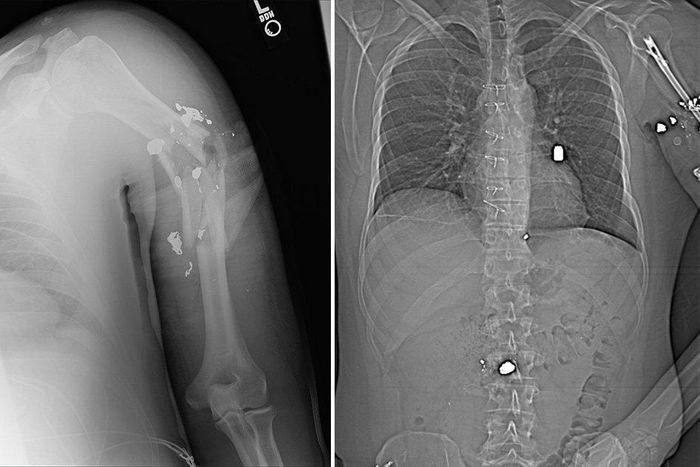

In all, Young had been shot a total of nine times: once in the upper left arm, three times in the back, once between the groin and femoral artery, once in his hip, once in his buttocks, once in the right femur, and once in his right arm below the elbow.

But he still has reminders of all that he's been through. There are bullets and shrapnel scattered throughout his body, many of which are too dangerous to remove. One is in the lower left lobe of his lung. Another is in his spine; if it migrates, doctors are worried that Young could lose his mobility. He even has one near his heart, which he has to get checked out every six months. "It's a miracle in itself that my heart could handle that, and I definitely give credit to being fit and a lot of help from above."